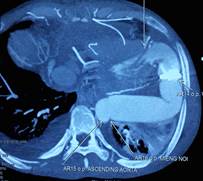

Khó khăn lớn nhất gặp phải khi thực hiện phẫu thuật cho bệnh nhân là không có vật liệu tiêu chuẩn để làm cầu nối. Đó là bộ vật liệu bao gồm ống nối cho mỏm tim, van tim nhân tạo và ống mạch nhân tạo. Các vật liệu này được thiết kế riêng cho phù hợp với việc luồn vào mỏm thất trái và đường đi của nó đến động mạch chủ xuống để không làm hẹp các miệng nối, đoạn gấp khúc và đảm bảo dẫn lưu đủ cung lượng tim [4]. Hiện ở Việt Nam chưa có bộ sản phẩm này trên thị trường. Để giải quyết vấn đề trên, chúng tôi sử dụng ống mạch nhân tạo số 27 để nối với mỏm thất trái, nối một ống mạch nhân tạo khác có gắn van (đầu ngoại vi) vào động mạch chủ xuống đoạn ngang mỏm tim. Sau đó hai đoạn này được nối lại với nhau để tạo thành một cầu nối tắt có van cho dòng máu di chuyển một chiều từ mỏm thất trái xuống động mạch chủ (Hình 4c,d,e,f,g). Lý do để chọn đoạn mạch có cỡ lớn như vậy là đề phòng trường hợp gấp khúc cầu nối dẫn đến gây hẹp và dẫn lưu không hết thể tích tống máu của thất trái. Kết quả chụp cắt lớp vi tính đa dãy đầu dò sau mổ cho thấy vẫn có tình trạng gấp khúc cầu nối trước và sau van nhân tạo (Hình 5) nhưng trên siêu âm thì chênh áp qua các chỗ này là không đáng kể cho thấy việc lựa chọn vật liệu là phù hợp.